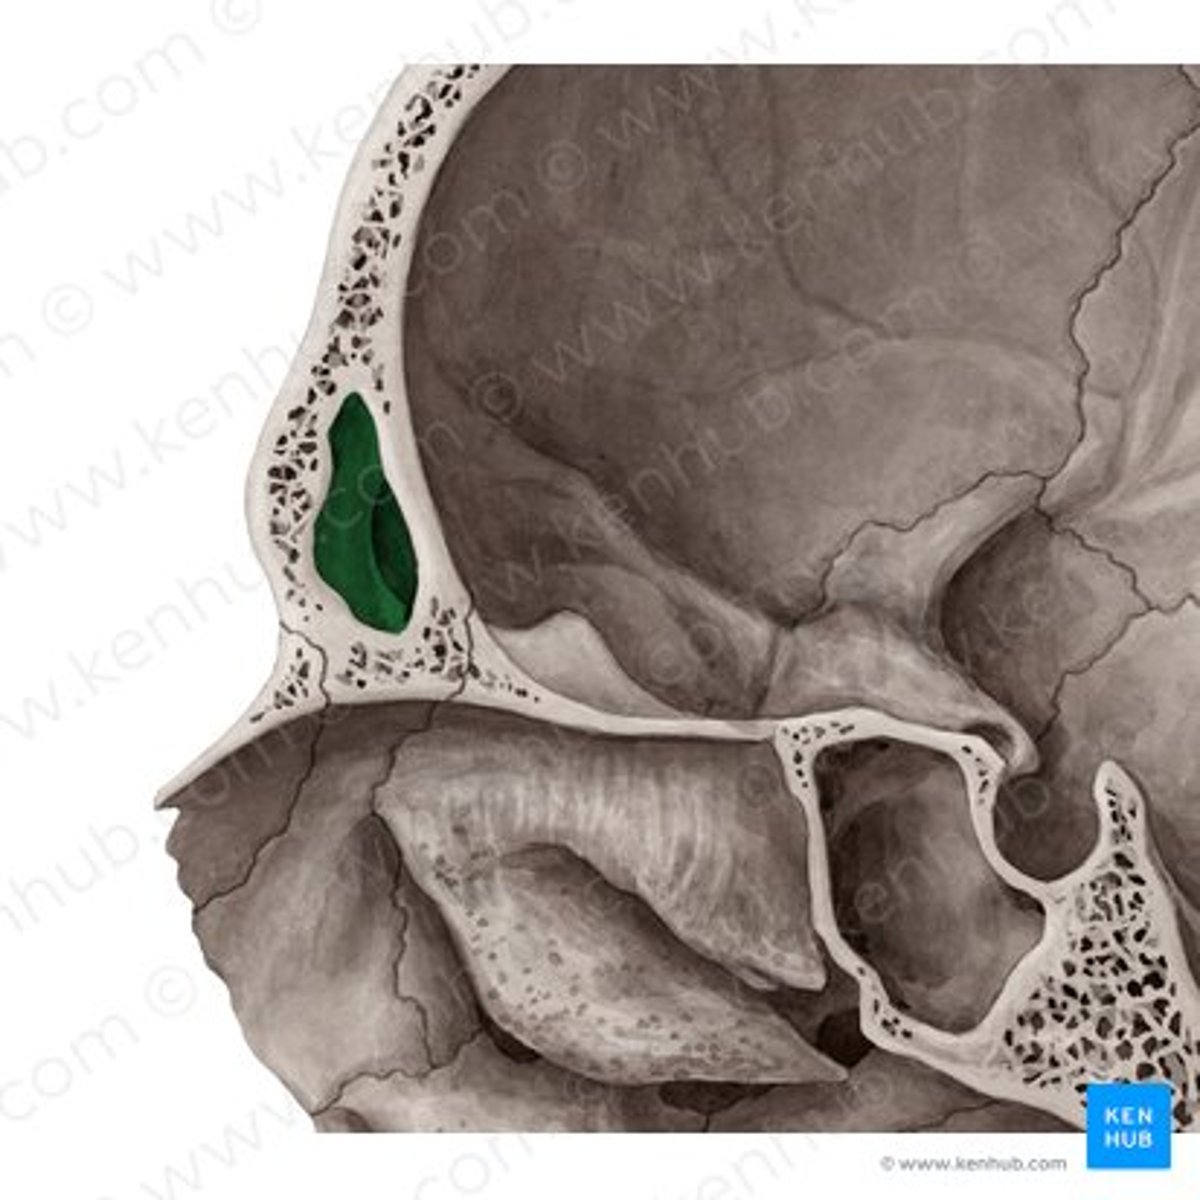

cribriform plate